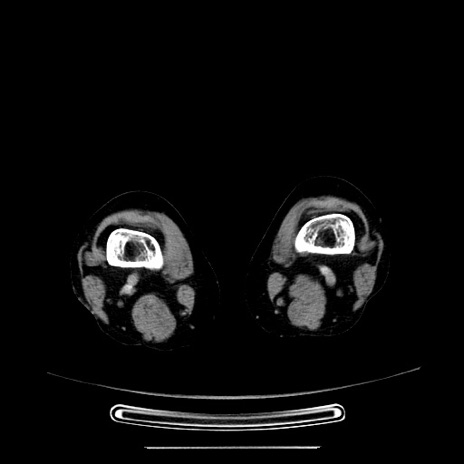

症例5(横断像)

【症例】70歳代女性

【主訴】お腹が張る

【現病歴】1週間くらい前から腹部膨満の自覚あり。昨日夜から増悪したため、本日救急外来受診。

【身体所見】意識清明、BT 36.5℃、BP 165/106mmHg、HR 80bpm、SpO2 98%、腹部:膨満、軟、自発痛・圧痛なし、触診にて不快感あり、腸蠕動音:減弱

【データ】WBC 12600、CRP 1.04